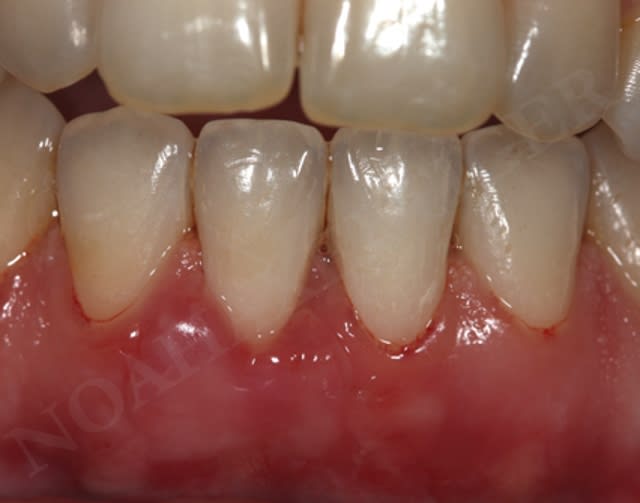

Par contre dans le cas suivant le but était de recréer un environnement gingival compatible avec une bonne santé parodontale :

Cicatrisation ohekde - Eugenol

Initial wy0cig - Eugenol

Greffe gingivale libre slhq1i - Eugenol

Cicatrisation sondage xk347o - Eugenol